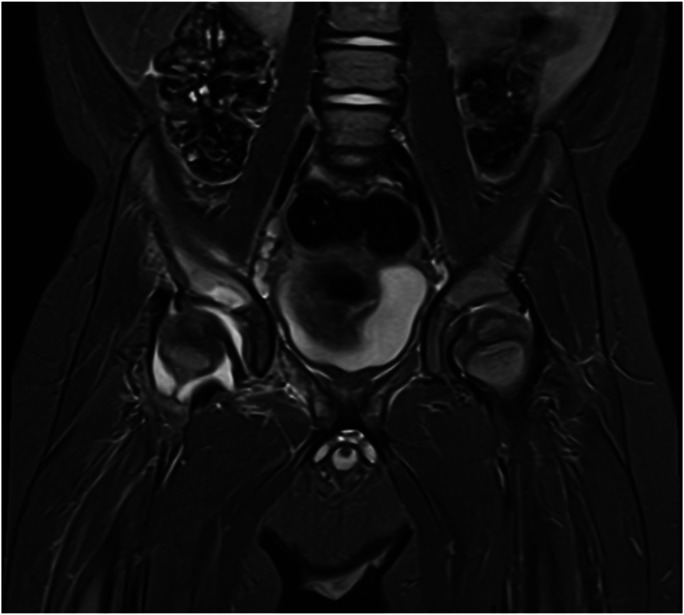

Abstract Image